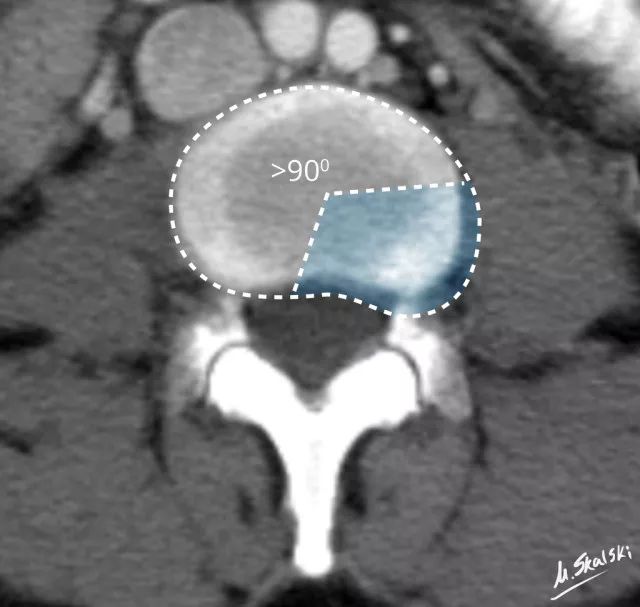

图 3 椎间盘膨出的影像学定义为突出部分>椎间盘边缘的25%,或者突出的两边与髓核的中心的夹角>90°